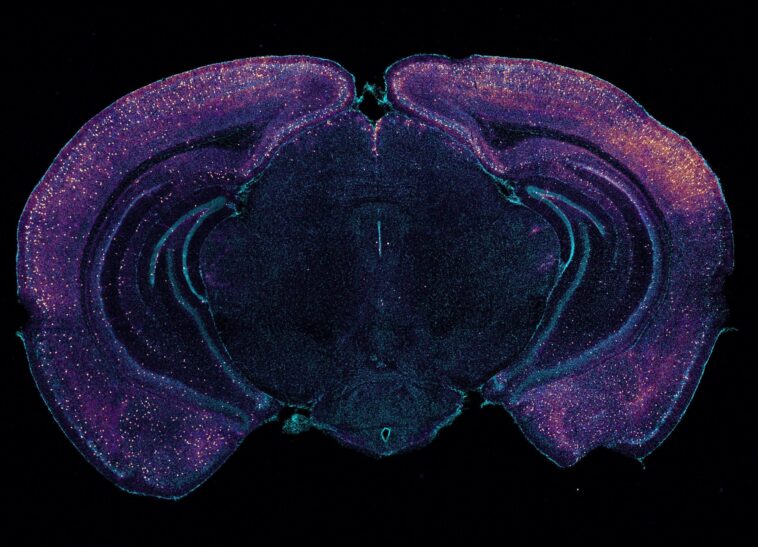

Une coloration brillante met en évidence les interneurones exprimant VIP dans cette coupe transversale coronale d’un cerveau de souris. Les neurones peuvent contribuer à la clairance glymphatique de l’amyloïde via la libération de peptides. Crédit : Laboratoire Tsai/Institut MIT Picower

Les données de séquençage de l’ARN ont également révélé que lors d’une stimulation sensorielle gamma, un sous-ensemble de neurones, appelés « interneurones », a connu une augmentation notable de la production de plusieurs peptides. Cela n’était pas surprenant dans le sens où la libération de peptides est connue pour dépendre des fréquences du rythme cérébral, mais cela restait remarquable car un peptide en particulier, le VIP, est associé aux bienfaits de la lutte contre la maladie d’Alzheimer et aide à réguler les cellules vasculaires, le flux sanguin et clairance glymphatique.

S’appuyant sur ce résultat intrigant, l’équipe a effectué des tests qui ont révélé une augmentation du VIP dans le cerveau des souris traitées aux rayons gamma. Les chercheurs ont également utilisé un capteur de libération de peptides et ont observé que la stimulation sensorielle gamma entraînait une augmentation de la libération de peptides par les interneurones exprimant VIP.